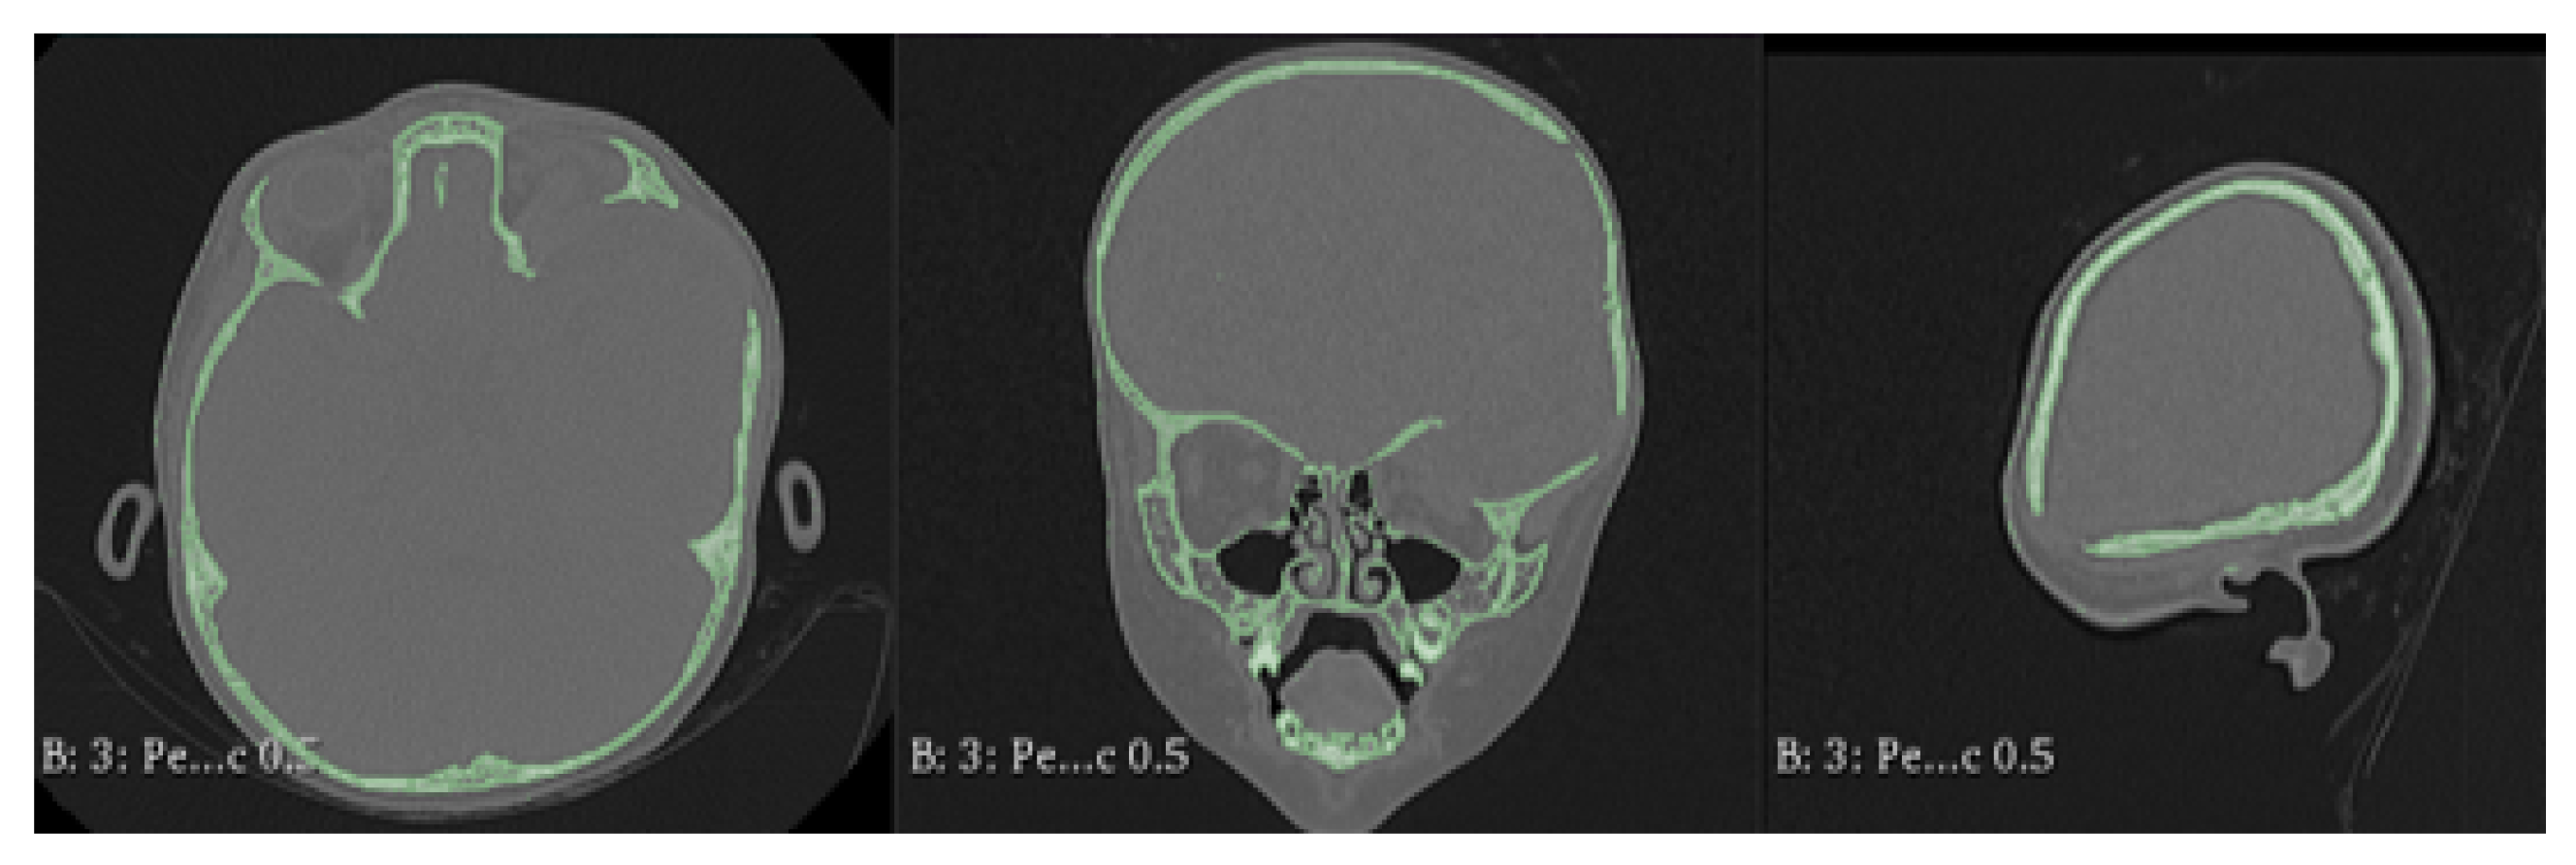

3.7.1. Diagnosis and Analysis

3.7.2. Surgical Planning

3.7.3. Design and Printing of Anatomical Models